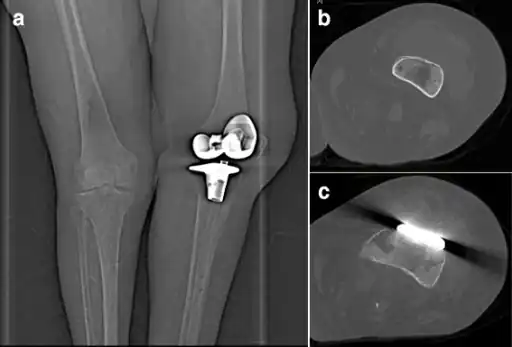

a)Frontal radiograph of the left knee demonstrates normal post-operative appearance of prosthesis with no prosthetic loosening b,c) computer tomography shows an abscess in front of knee prosthesis caused by Pasteurella multocida